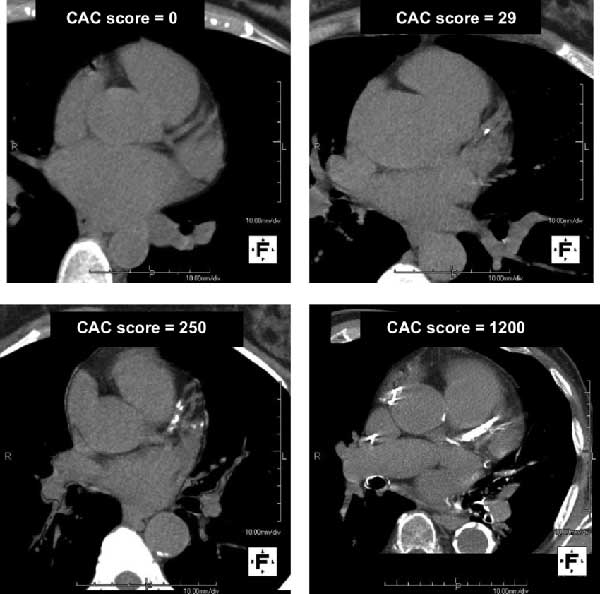

As a Cardiologist Who Has Reported on 1000's of Cardiac CT Scans

Here Are 5 Things I Wish Everyone Knew About Them

To Maximally Reduce Their Future Risk Of A Heart Attack. Image

1. A CT Coronary Calcium (CAC) Score of 0

Suggests a VERY LOW RISK of a heart attack over the next 10 years.

About 2-3%.

Thats amazing.

If you are 70.

But if you are 40

You have MANY more 10-year blocks ahead of you, so you need to keep that in mind. Image

2. A CAC Score Of Even 1 At

Under 55 For Males or

Under 65 For Females

Means you are accumulating plaque earlier than an age matched average peer.

Your NEAR term risk is not high but you are pulling it forward.

Always ASK what percentile your score is. Image